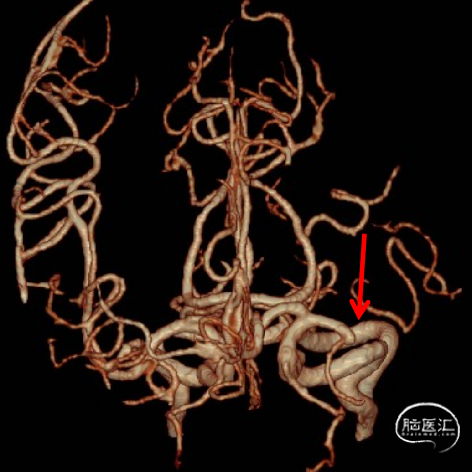

DSA

1、急性脑梗死。2、左侧大脑中动脉M1段闭塞。

ICAS合并血栓?

夹层合并血栓?

栓塞?

微导管通过后,结合首过效应、支架释放效应等决定取栓及后续策略。